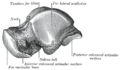

Though irregular in shape, the talus can be subdivided into three parts.

Facing anteriorly, the head carries the articulate surface of the navicular bone, and the neck, the roughened area between the body and the head, has small vascular channels.[2]

The body features several prominent articulate surfaces: On its superior side is the trochlea tali, which is semi-cylindrical,[4] and it is flanked by the articulate facets for the two malleoli.[2] The ankle mortise, the fork-like structure of the malleoli, holds these three articulate surfaces in a steady grip, which guarantees the stability of the ankle joint. However, because the trochlea is wider in front than at the back (approximately 5–6 mm) the stability in the joint vary with the position of the foot: with the foot dorsiflexed (toes pulled upward) the ligaments of the joint are kept stretched, which guarantees the stability of the joint; but with the foot plantarflexed (as when standing on the toes) the narrower width of the trochlea causes the stability to decrease.[5] Behind the trochlea is a posterior process with a medial and a lateral tubercle separated by a groove for the tendon of the flexor hallucis longus. , the lateral of these tubercles forms an independent bone called os trigonum or "accessory talus"; it may represent the tarsale proximale intermedium. On the bone's inferior side, three articular surfaces serve for the articulation with the calcaneus, and several variously developed articular surfaces exist for the articulation with ligaments.[2]

For descriptive purposes the talus bone is divided into three sections, neck, body, and head.

The neck of talus is directed anteromedially, and comprises the constricted portion of the bone between the body and the oval head.[6]

Its upper and medial surfaces are rough, for the attachment of ligaments; its lateral surface is concave and is continuous below with the deep groove for the interosseous talocalcaneal ligament.[6]